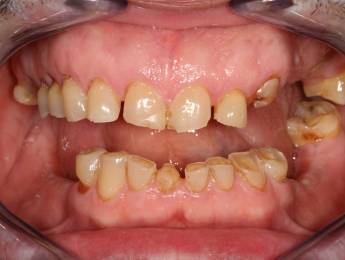

6. Eset

Nagymértékű fogkopás, erózió, csikorgatás a teljes rágóapparátust túlterhelve okoz reménytelennek tűnő helyzeteket.

Ebben az esetben implantátumok , koronák és hidak segítségével változtattunk a páciens fogainak érintkezésén. 6 hónapig ideiglenes hidakkal teszteltük a megváltoztatott harapási pozíciót. Ezután készültek el a végleges fix pótlások.